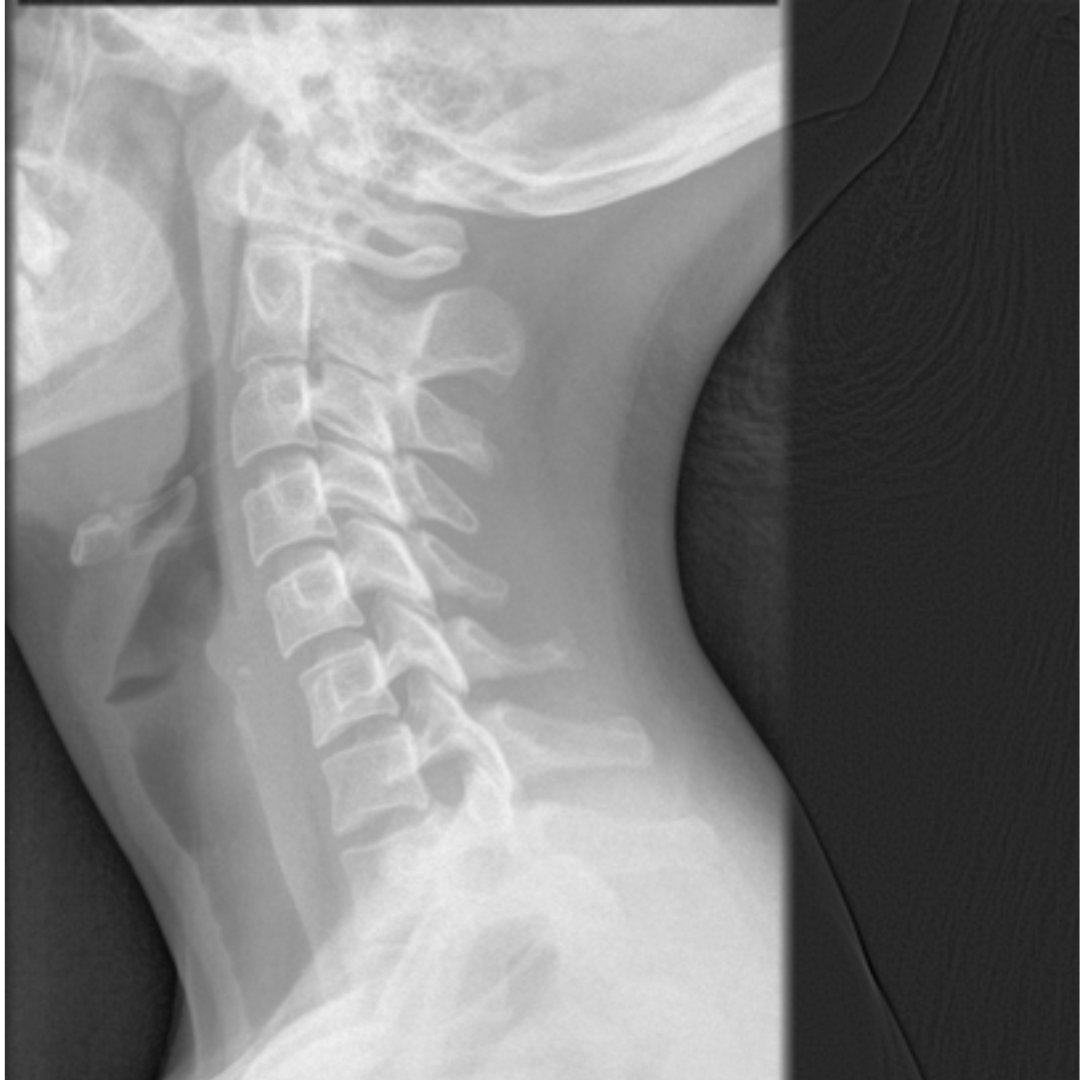

頸椎側面撮影 頸椎は、Cと略して呼ぶこともあります! 第1頸椎(環椎)は C1。

頸椎は、Cと略して呼ぶこともあります!

第1頸椎(環椎)は C1。